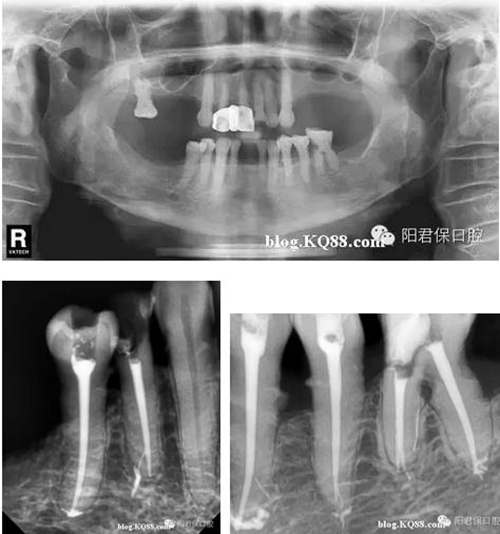

患者:姜XX 性別;女 年齡:65 根據(jù)齲壞程度、患者的癥狀、修復(fù)需要,且對收費及牙髓處理均征得同意后第一次行右下4、5,左下4、5、6;第二次行左下2,右下2 ,右上7一次性根管治療術(shù)。

術(shù)后見右下4,左下4均有側(cè)支充填,且位置對稱,左下6近中根中部有側(cè)支;左下5、左下6遠中根管均多個開口。

熱牙膠垂直加壓后有封閉劑和牙膠超填,但無術(shù)后反應(yīng)。